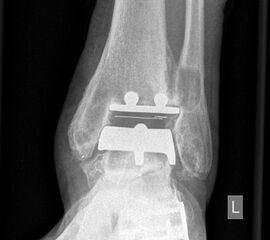

• Prothesenplanung anhand von Röntgenschablonen (Abb. 1 und 2).

• Röntgenkontrollen: 2 Tage postoperativ, 6 Wochen postoperativ; 3, 6, 12 Monate postoperativ, dann im Abstand von 12-18 Monaten.

Im Zeitraum zwischen 2006-2010 analysierten wir 118 SALTO-OSG-Prothesen bei 118 Patienten, 67 (56,8%) ohne zusätzliche Rückfußeingriffe, 51 (43,2%) mit zusätzlicher Rückfußkorrektur. Die Patienten wurden klinisch und radiologisch nachuntersucht. Das mittlere Follow up betrug 36 Monate.